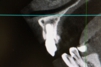

根の先に影(感染)が出てしまい根の治療を行わないといけないのですが以前他院にて処置を施した古い薬が入っています

画像を見ると手前の根にはしっかりと先まで薬が入っていません(1枚目の画像)

根のカーブに対応できず間違った方向へ削り込んでしまっています(赤矢印)

古い薬を除去しとあるテクニックを駆使し正しい根幹への道を見つけました(青矢印)

簡単にやっているように見えますがそのまま器具を入れては大きく間違った道に導かれてしまうなか、その脇から1mmにも満たない狭く曲がった孔を探しそちらへ導くのは至難の技ですが、マイクロスコープとCTを使いしっかりとした手法で行うとこのような症例にも対応できます